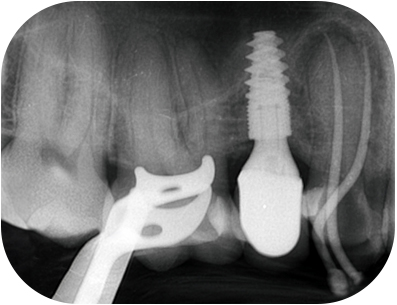

prémolaire, le composite présente une étanchéité insuffisanteFig. 01 : Ie composite présente une étanchéité insuffisante, notamment avec la reprise

d’une lésion carieuse en distal.

prémolaire, la LIPOE Fig. 02 : la LIPOE est centrée sur la racine

palatine et le canal est clairement

identifiable au CBCT.